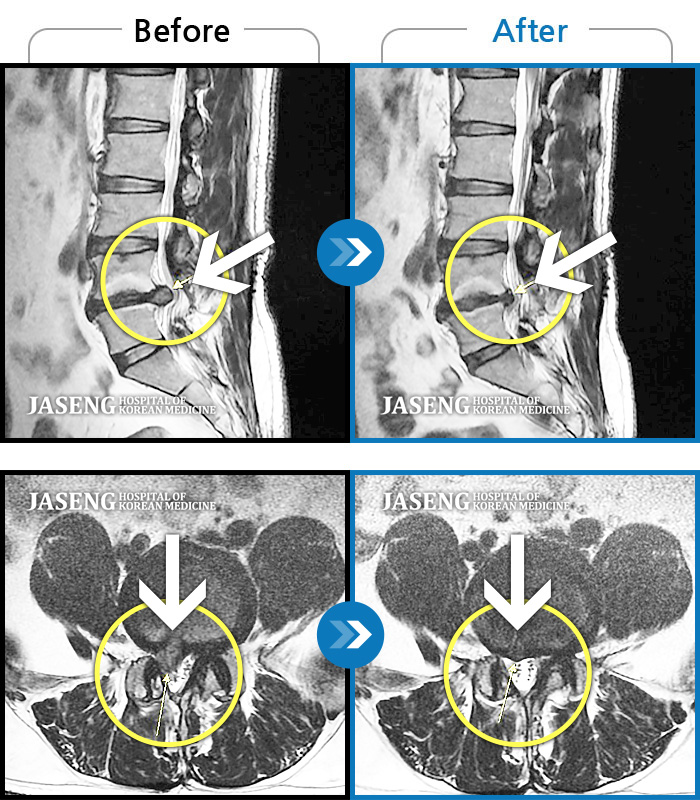

허리디스크

울산 · 정운석 원장

하요추부 통증과 양측 대퇴부 후면 저림

촬영시기

2020.01.10 ~ 2022.08.20

2022.08.26